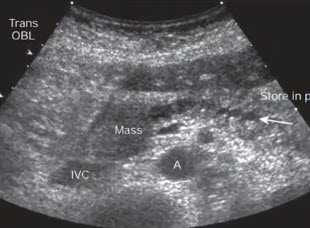

- Поперечное сканирование в эпигастральной области. Образование в головке (Mass), приводящее обструкции панкреатического протока. Четкообразное неравномерное расширение протока (стрелка). А - аорта, IVC - нижняя полая вена

- Косое сканирование в эпигастральной области. Гипоэхогенное образование в хвосте поджелудочной железы (ПЖ)